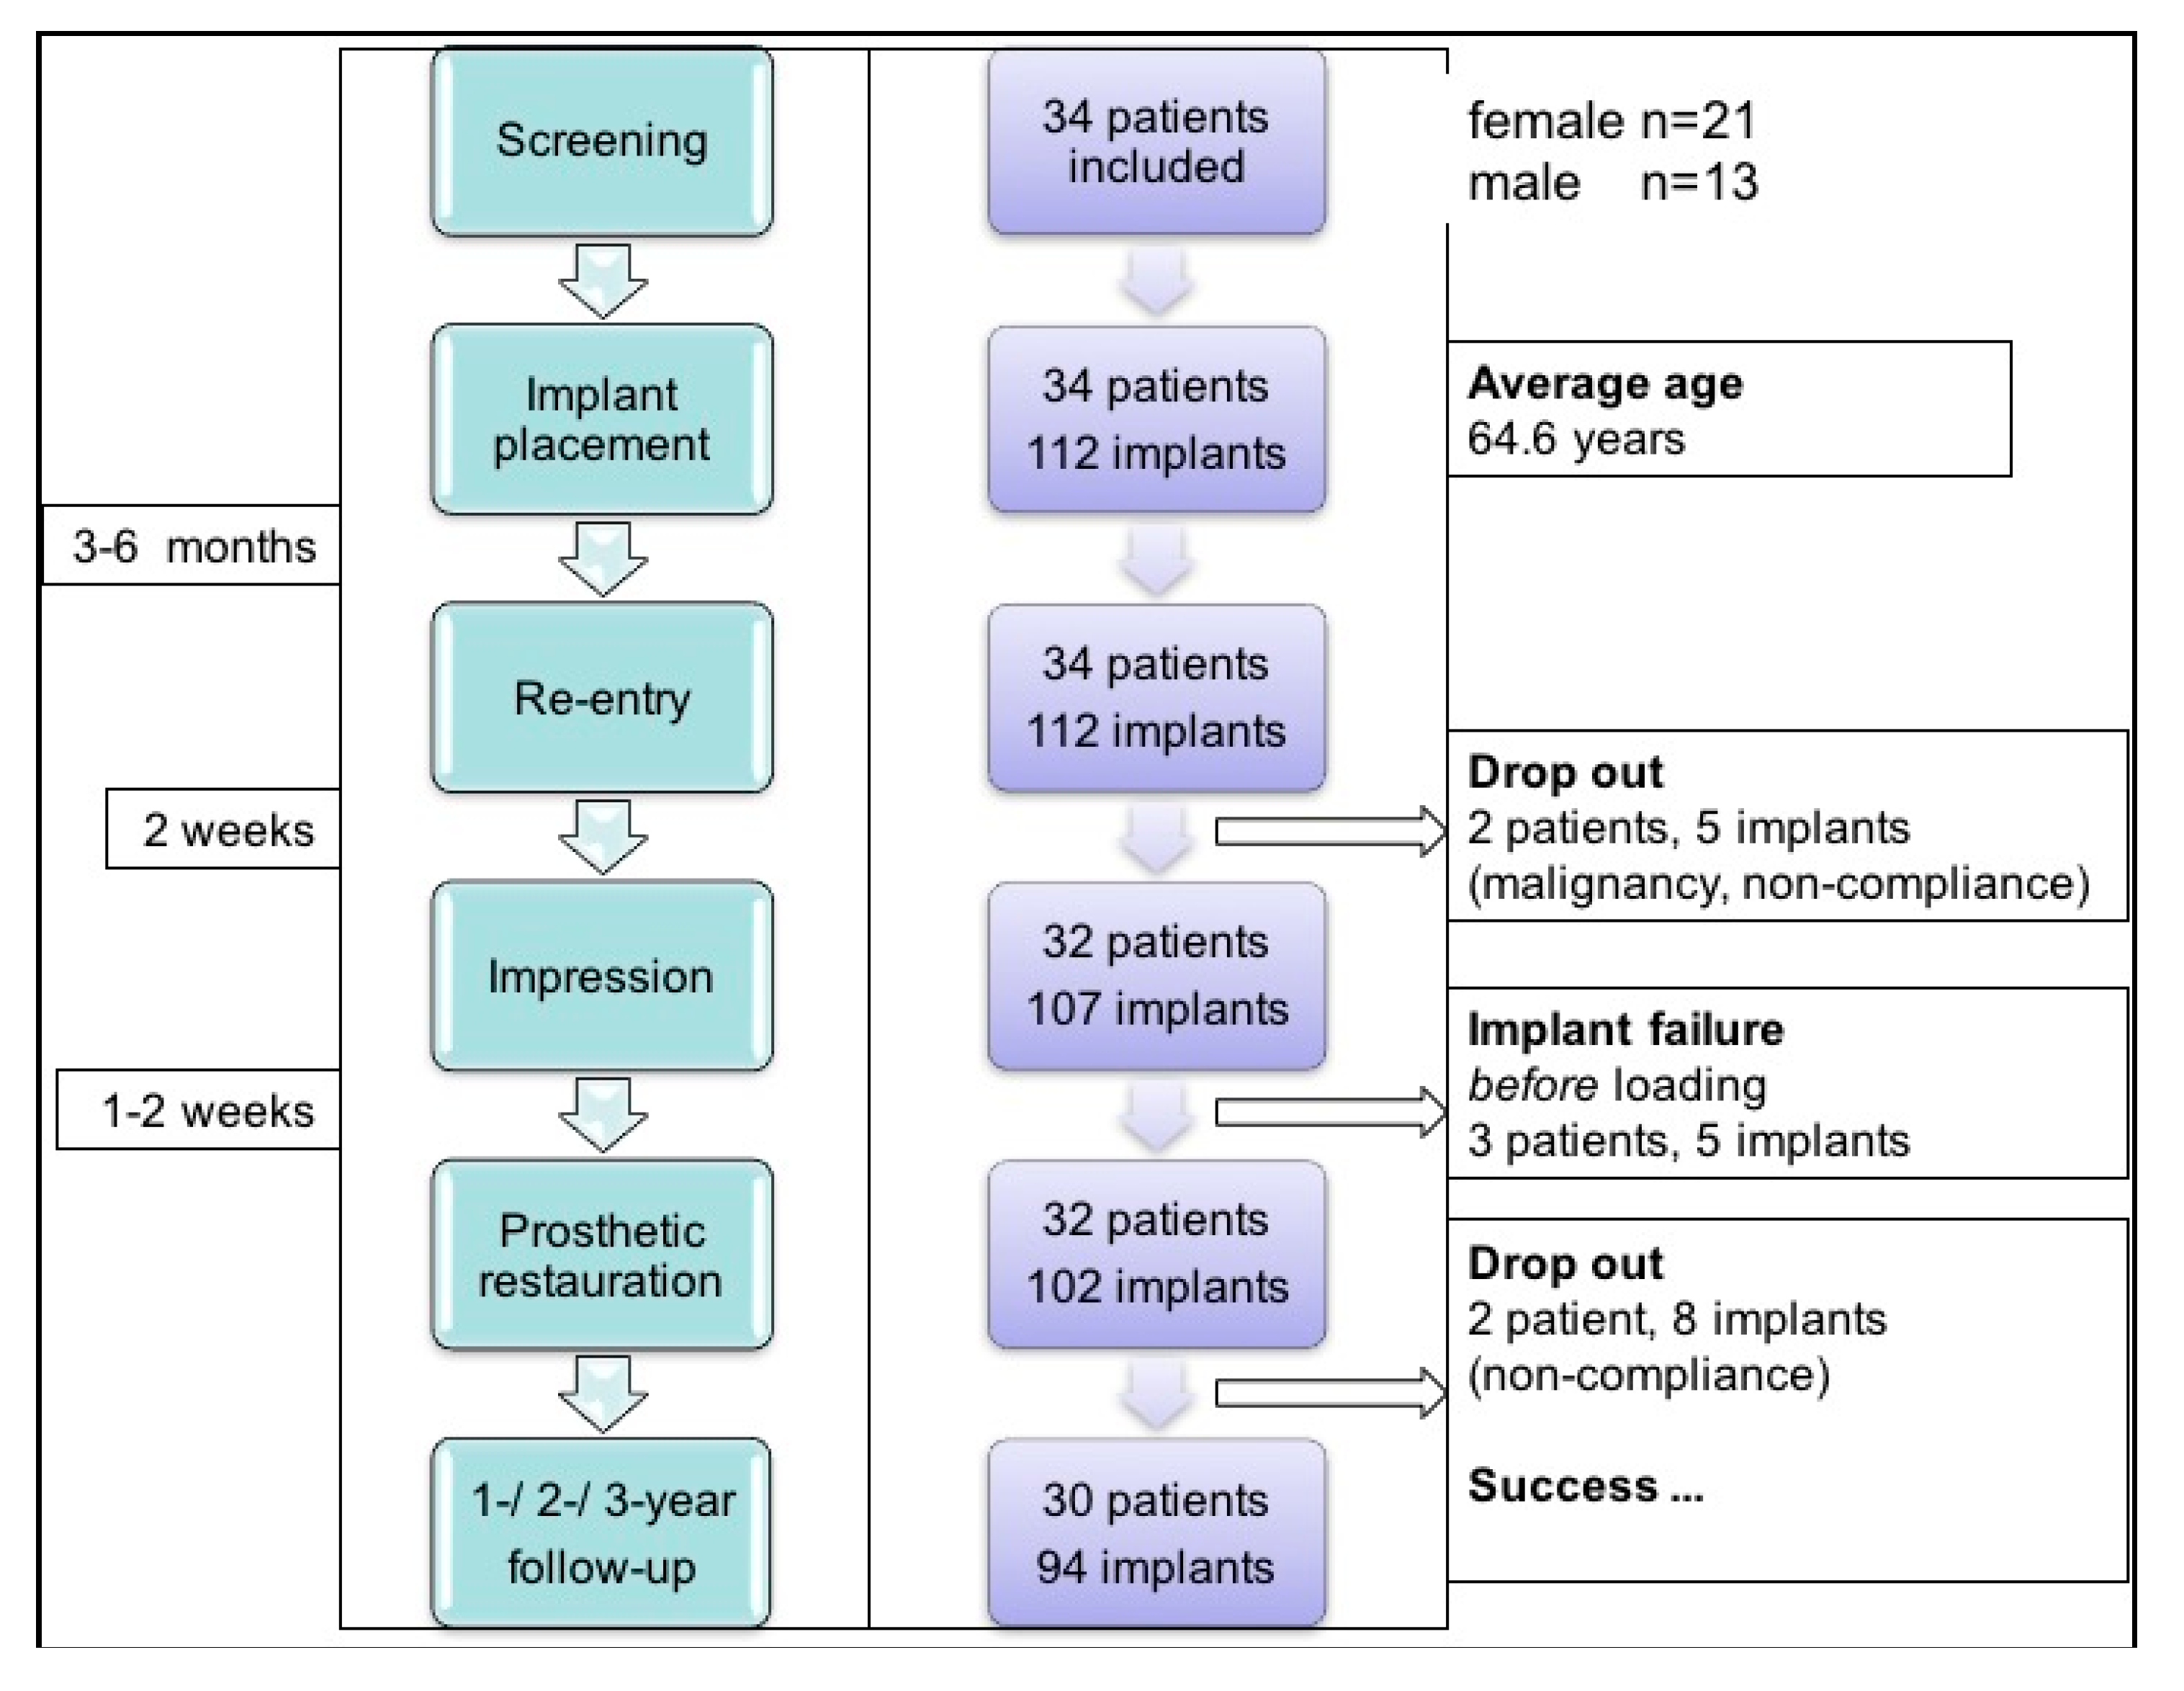

3.1. Study Population